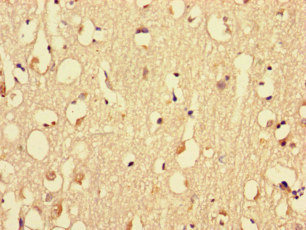

ELISAIHCIF

IHC

1:20-1:200